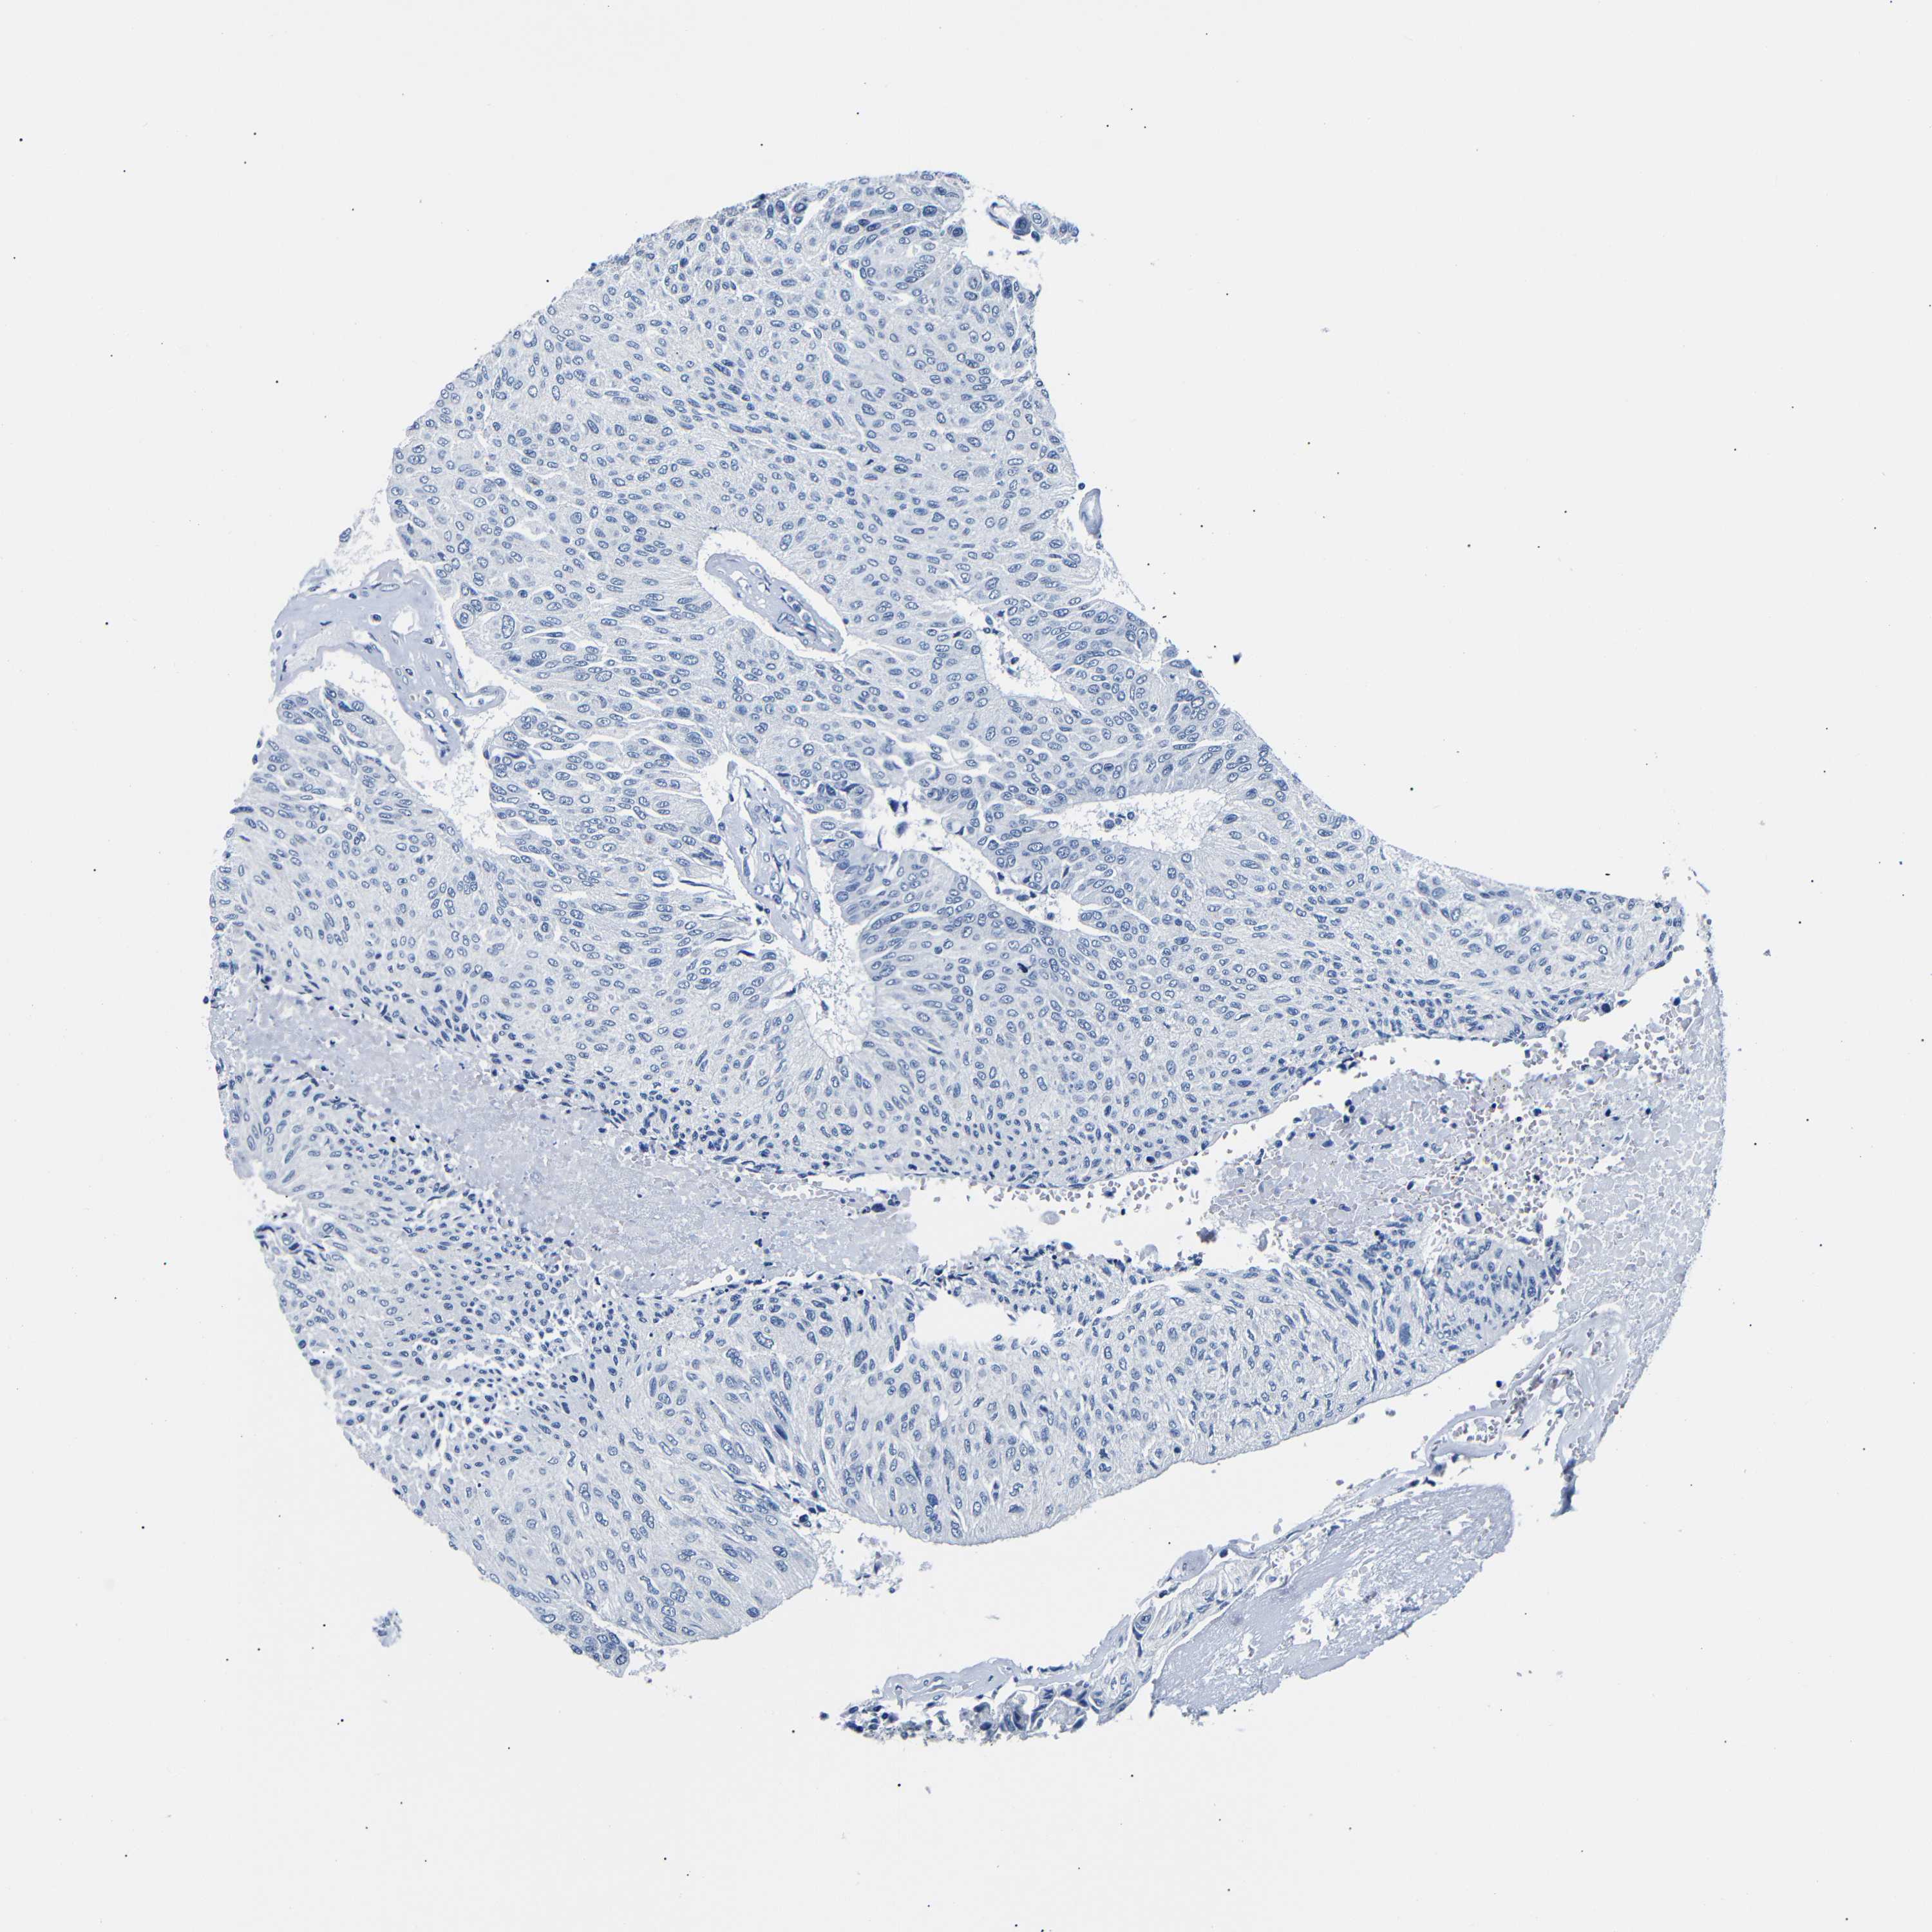

UROTHELIAL CANCER - Protein expressioni

A mouse-over function shows sample information and annotation data. Click on an image to view it in a full screen mode. Samples can be filtered based on level of antibody staining by selecting one or several of the following categories: high, medium, low and not detected. The assay and annotation is described here.

Antibody stainingi

Antibody staining in the annotated cell types in the current human tissue is reported as not detected, low, medium, or high, based on conventional immunohistochemistry profiling in selected tissues. This score is based on the combination of the staining intensity and fraction of stained cells.

Each image is clickable and will lead to virtual microscopy that enables deeper exploration of all samples and also displays staining intensity scores, fraction scores and subcellular localization as well as patient and tissue information for each sample.

Antibody HPA013392

Antibody HPA015600

Antibody CAB004417

Staining

High

Medium

Low

Not detected

Intensity

Strong

Moderate

Weak

Negative

Quantity

>75%

75%-25%

<25%

None

Location

Nuclear

Cytoplasmic/membranous

Cytoplasmic/membranous,nuclear

Urothelial carcinoma, Low grade

Urothelial carcinoma, High grade